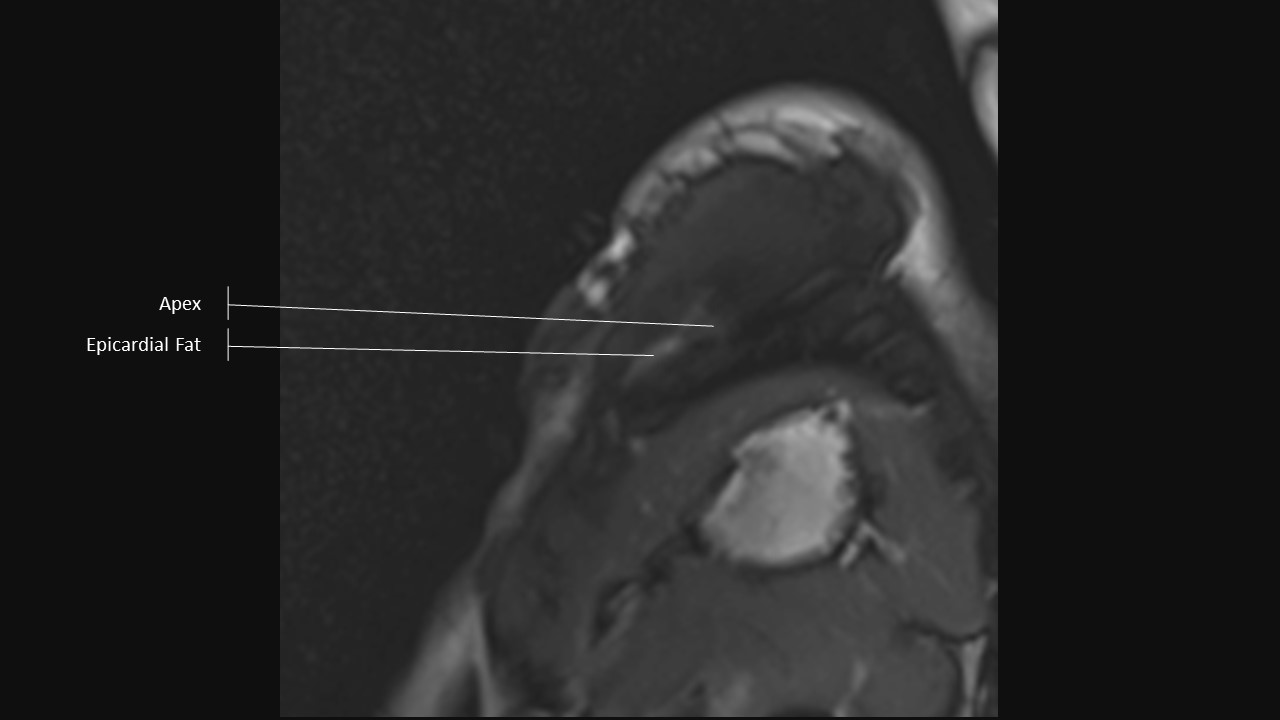

Short Axis Series